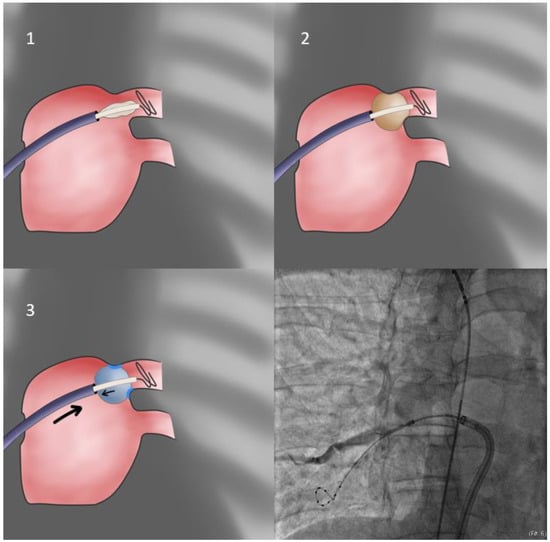

- In cases of cranial superior veins and horizontal inferior veins, we apply the CB-only approach (Figure 3) without the sheath (second approach). The sheath is relaxed and placed near but not in contact with the CB since even minimal flexion to the sheath will preclude proper sealing of the antrum. Selection of the more horizontal branch of the PV facilitates the CB-only approach, even if repositioning of the Achieve catheter is required. Additionally, cranial flexion of the CB shaft assists cranial superior PV sealing.